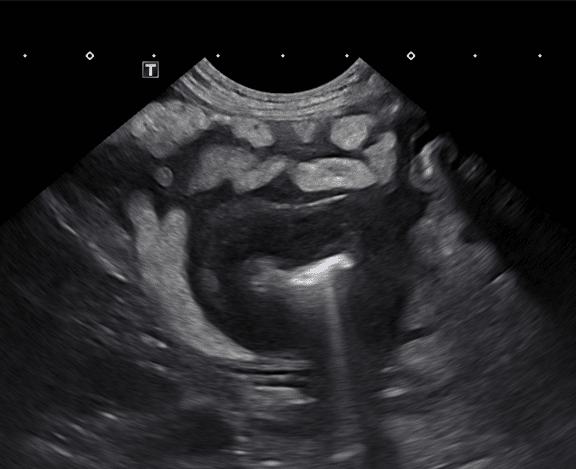

Small intestinal abnormalities on ultrasound can be broken into two main categories: focal and diffuse disease. Focal small intestinal lesions include mechanical obstruction caused by foreign material, intussusception, or a mass. Masses are described as circumferential, asymmetrically circumferential, or eccentric (Figures 1a-1c). In dogs, one study noted that 99% of dogs with intestinal neoplasia have a loss of wall layering; unfortunately, there can be some overlap between benign and malignant masses on ultrasound. The more common intestinal mass neoplasms include adenocarcinoma, lymphoma, gastrointestinal stromal tumor, leiomyosarcoma, leiomyoma, and mast cell tumor. In cats, the most common intestinal masses are lymphoma or adenocarcinoma, followed by mast cell tumors. Lymphoma can present as solitary or multiple masses or a diffuse altered wall layering. Carcinomas most often are transmural lesions with loss of wall layering and can result in the narrowing of the lumen and secondary mechanical ileus. Mast cell tumors most commonly present as a focal mass that is hypoechoic and either eccentric or asymmetrically circumferential, similar to other intestinal neoplasms, and is rarely reported as a diffuse intestinal wall thickening. An interesting point documented in cats is that mast cell tumors in the intestine can often alter but not completely disrupt the wall layering. In dogs, it has been reported that there are no ultrasonographic signs to help differentiate between gastrointestinal spindle cell tumor types as they most often are seen as eccentric and bulging out of the serosa; however, gastrointestinal stromal tumors were more commonly seen in the cecum and large intestine.

Figure 1c (above): Example of an asymmetric, circumferential small intestinal mural mass diagnosed as lymphoma.